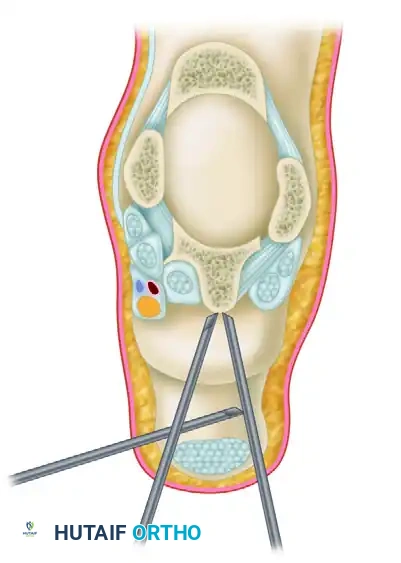

The posteromedial portal is established at the exact same horizontal level as the posterolateral portal, but positioned just medial to the medial border of the Achilles tendon.

Make a superficial skin incision. Insert a blunt hemostat through the incision, directing it laterally to contact the shaft of the arthroscope (which is already seated in the posterolateral portal) at a 90-degree angle.

Once the hemostat makes tactile metal-on-metal contact with the arthroscope shaft, slide the hemostat anteriorly down the shaft until it hits the bone and enters the arthroscopic field of view. This "sliding" technique ensures the instrument bypasses the posteromedial neurovascular bundle safely. If desired, or if the anatomy is distorted, utilize intraoperative fluoroscopy to confirm the appropriate placement of the instruments before introducing motorized shavers.